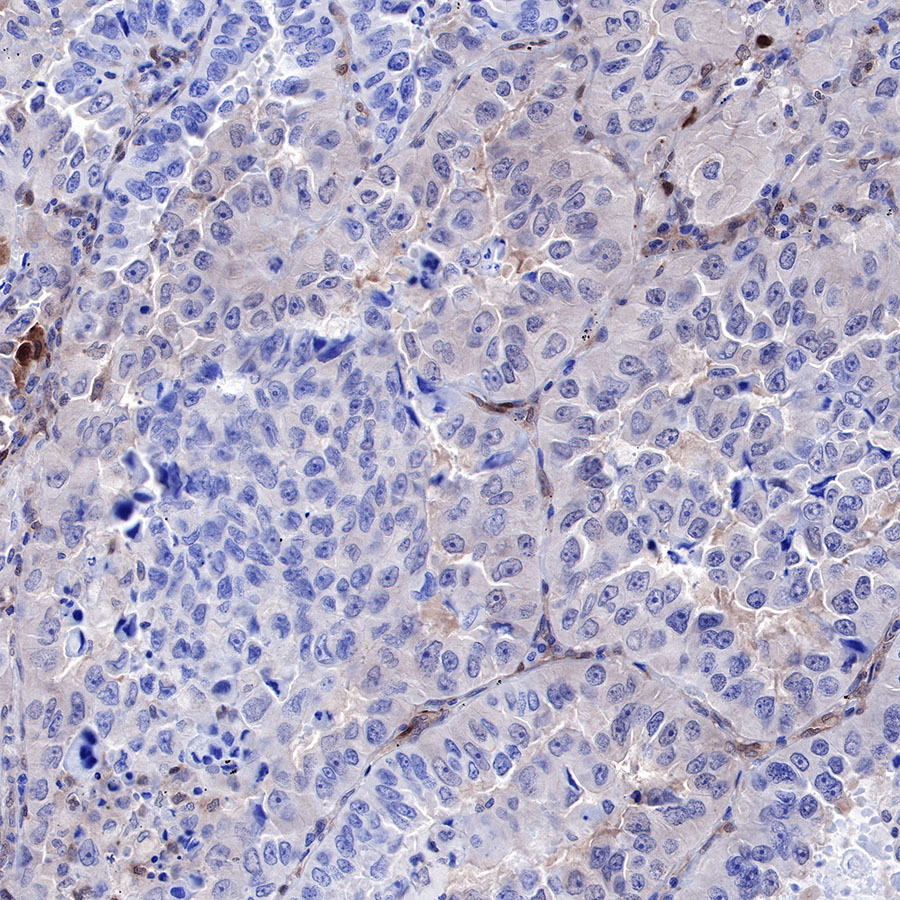

Immunohistochemistry

IHC shows positive staining in paraffin-embedded human lung cancer. Anti-PTEN antibody was used at 1/500 dilution, followed by a HRP Polymer for Mouse & Rabbit IgG (ready to use). Counterstained with hematoxylin. Heat mediated antigen retrieval with Tris/EDTA buffer pH9.0 was performed before commencing with IHC staining protocol.